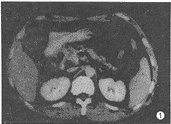

CT表现:(1)胰头轻度增大2例,约3.5cm×3.0cm,胰体、尾部相对缩小;胰钩突饱满、圆隆、分叶9例。 (2)胰头局限性低密度区5例(图1),大小约1.5cm×1.5cm~3.0cm×3.0cm,2例位于胰头前部,向外突起,边界较清楚,3例位于胰头内,边界不清,与胰腺组织呈移行状。2例胰头增大伴有弥漫性密度轻度减低,9例胰钩突密度减低,其中1例密度显著减低,但形态正常。十二指肠降部内侧壁局限性结节3例(图2),大小约1.5cm×2.0cm~2.0cm×2.0cm,密度与软组织相同,边缘清楚。增强扫描胰头病灶呈低密度或不均匀低密度区,十二指肠内侧壁结节有明显强化。 (3)胆总管下端软组织结节、局部管壁增厚、下段管壁均匀增厚各1例(图3),肝内胆管扩张18例,胆总管扩张19例,胆总管下端突然中断16例,逐渐变窄3例,胰管扩张19例。

图1 胰头腺癌。胰头内局限性低密度区,形态不规则,边缘不清楚,伴有胰、胆管扩张 图2 Vater's壶腹绒毛腺瘤恶变。CT表现为胆总管下端结节,突入十二指肠内侧壁 图3 胆总管癌。胆总管壁均匀增厚,有强化,与周围胰头分界不清,与炎症表现相似,手术见肿瘤沿胆总管壁浸润,达肝门,并有肝门淋巴结转移 图4 胰头炎症。胰头弥漫性肿大,内见散在小点状低密度区,其间胰头实质密度均匀,胰头与十二指肠紧密粘连 图5胆总管下端炎症。CT表现为胆总管下端一侧壁局限性增厚,以上胆道有少许积气,病理切片可见纤维组织增生及慢性炎细胞浸润 图6 胰头癌合并炎症。胰头后部(腔静脉左前侧)见边缘模糊小低密度区,于胰颈部有一炎性假囊肿